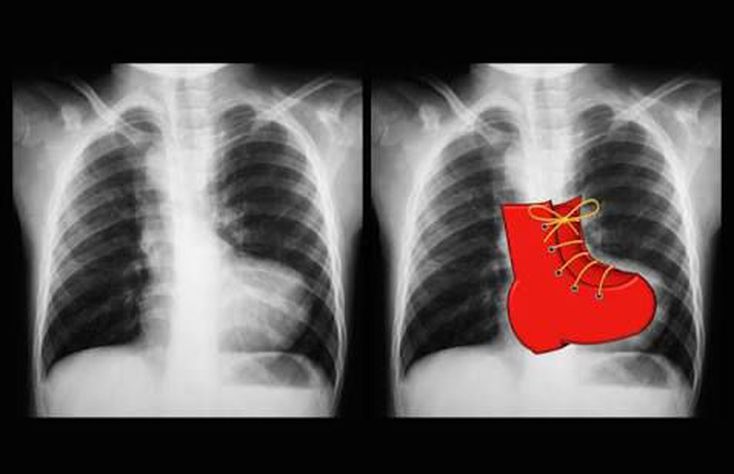

A 'boot-shaped' heart ("cœur en sabot" in French) is the description given to the appearance of the heart on plain film in some cases of Tetralogy of Fallot. It describes the appearances of an upturned cardiac apex due to right ventricular hypertrophy and a concave pulmonary arterial segment.